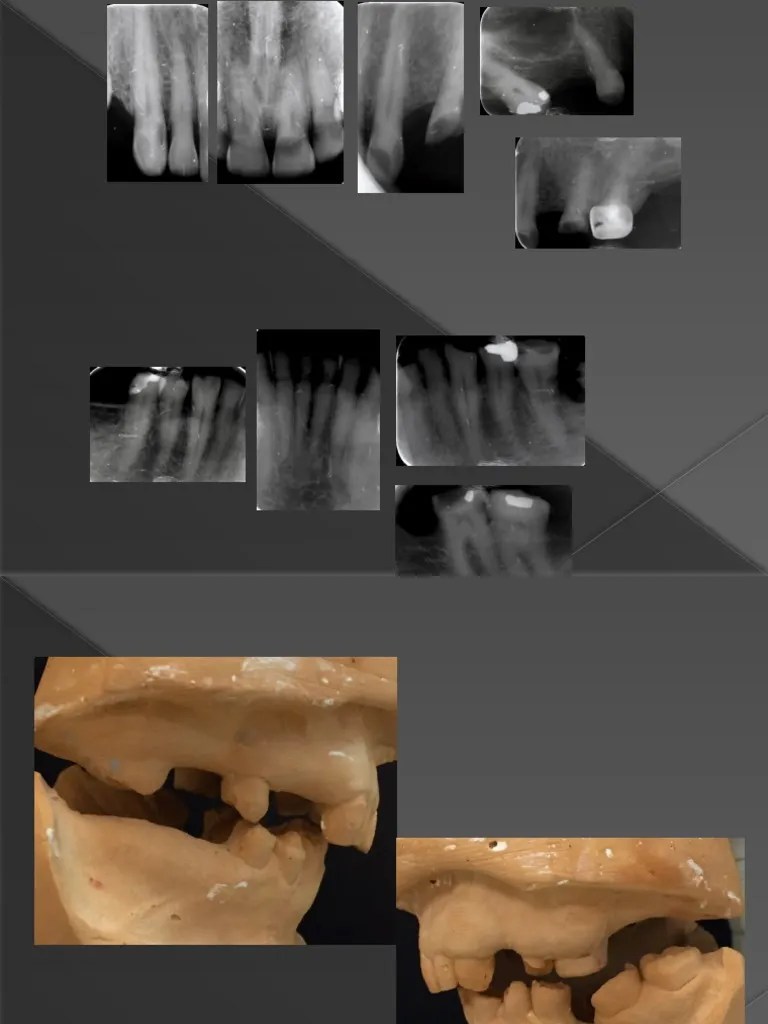

12 Diagnosis and Management of Dental Caries Pocket Dentistry What Does Occ Mean In Dentistry Occ in dentistry commonly refers to occlusal, which pertains to the surface of the teeth that comes into contact with the opposing teeth during chewing. Learn the terminology and how medical. A whole new language dental ce course & enrich your knowledge in oral. • define and pronounce the key terms in this chapter. Here you have your dental vocabulary. What Does Occ Mean In Dentistry.

Large PARL Healing after Orthograde Endodontic Treatment ADS What Does Occ Mean In Dentistry From root canals to extractions, dental terminology abbreviations,. • describe centric occlusion and its relationship to functional movements and patterns of the mandible. Here you have your dental vocabulary and dentist medical terminology for the procedures that dentists perform. Learn the terminology and how medical. An o, which stands for occlusal, is the top surface of a back tooth. A. What Does Occ Mean In Dentistry.